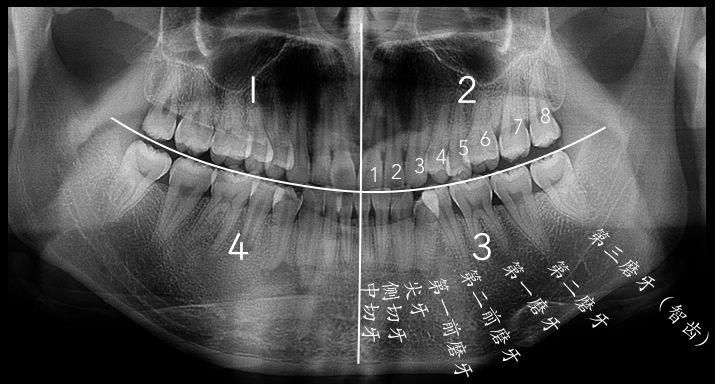

智齒的形態(tài)拔智齒的收費依據(jù)價格的背后——牙醫(yī)知識的凝聚常見智齒的形態(tài)智齒是從正中的門牙往里數(shù)第八顆牙齒,也就是第三顆磨牙。它是發(fā)育、萌出晚的牙齒,通常在4~5歲時形成牙胚,隨后逐漸發(fā)育形成牙齒,一般17~25歲左右萌出,此時人的生理、心理發(fā)育都接近成熟,因此俗稱“智齒”。

智齒的形態(tài)也是各種各樣,簡單可以羅列如下幾種,實際復雜遠不止以下:

1、垂直高位

2、舌向高位

3、前傾高位

4、水平高位

5、垂直中位

6、舌向中位

7、前傾中位

8、水平中位

9、垂直低位

10、舌向低位

11、前傾低位

12、水平低位

拔智齒的收費依據(jù)智齒位置、結(jié)構(gòu)、生長形態(tài)各不相同,這也直接導致拔除的難易程度各不相等。

下面這個圖可以簡單對價格做一個衡量,但不同地方、不同拔牙方法,收費差異不同,僅供參考。